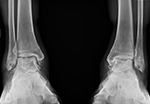

Our standing xray protocol is used to determine the overall shape, structure and integrity of the ankle and foot, while facilitating a comparison with the opposite side. The x-rays also assist in the evaluation of associated conditions.